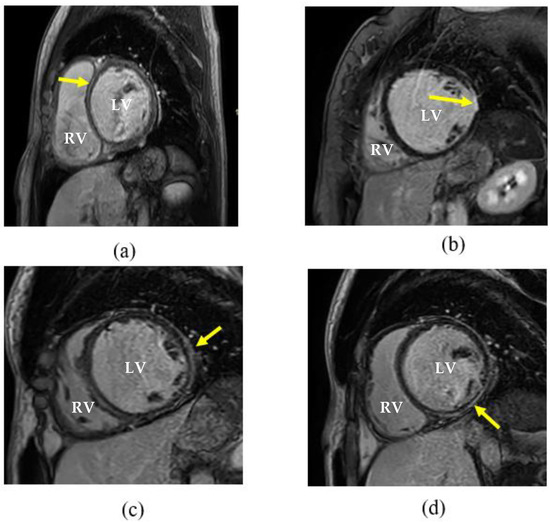

3.2. Cardiovascular Magnetic Resonance Imaging